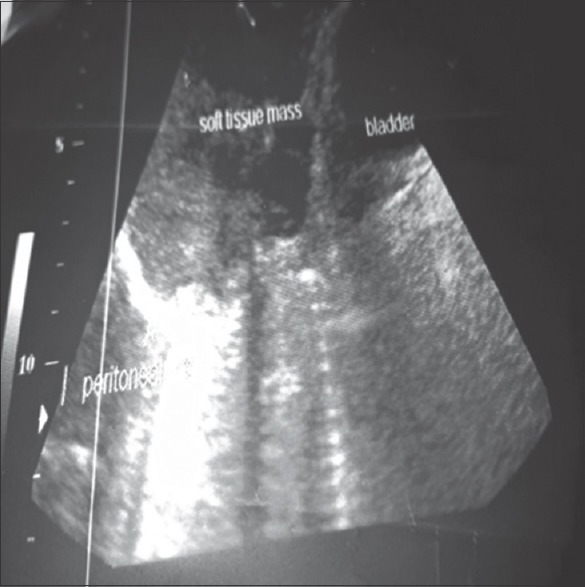

Desmoid fibromatosis (desmoid tumors) is rare tumors. It can occur as intra-abdominal, extraabdominal, or abdominal wall tumor depending on the site. The abdominal wall type is usually sporadic, but few have been associated with familial adenomatous polyposis. They are commonly seen in young females who are pregnant with a history of the previous cesarean section scar or within the 1st year of the last childbirth. There is an association between this tumor, presence of estrogen receptors, and abdominal trauma. We present a 29-year-old Nigerian woman with fungating lower abdominal wall tumor. This tumor is rare, a high index of suspicion will be very important in making the diagnosis.